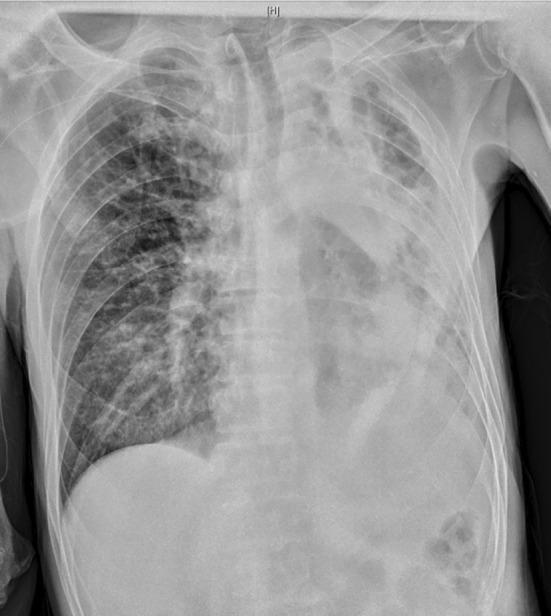

is a major pathogen in hospital-acquired infections notorious for its strong acquired resistance and complex drug resistance mechanisms. Owing to the lack of effective drugs, the mortality rate of extensively drug-resistant pneumonia can reach as high as 65%. This article analyzes a case where a combination of cefoperazone-sulbactam, polymyxin B, and minocycline with rifampicin successfully treated XDR-AB pulmonary infection. Combination therapy is effective and has a particular clinical value.

是医院获得性感染中的主要病原体,以其强大的获得性耐药性和复杂的耐药机制而臭名昭著。由于缺乏有效的药物,广泛耐药性肺炎的死亡率可高达65%。本文分析了一例头孢哌酮-舒巴坦、多粘菌素B、米诺环素联合利福平成功治疗XDR-AB肺部感染的病例。联合治疗有效,具有特殊的临床价值。